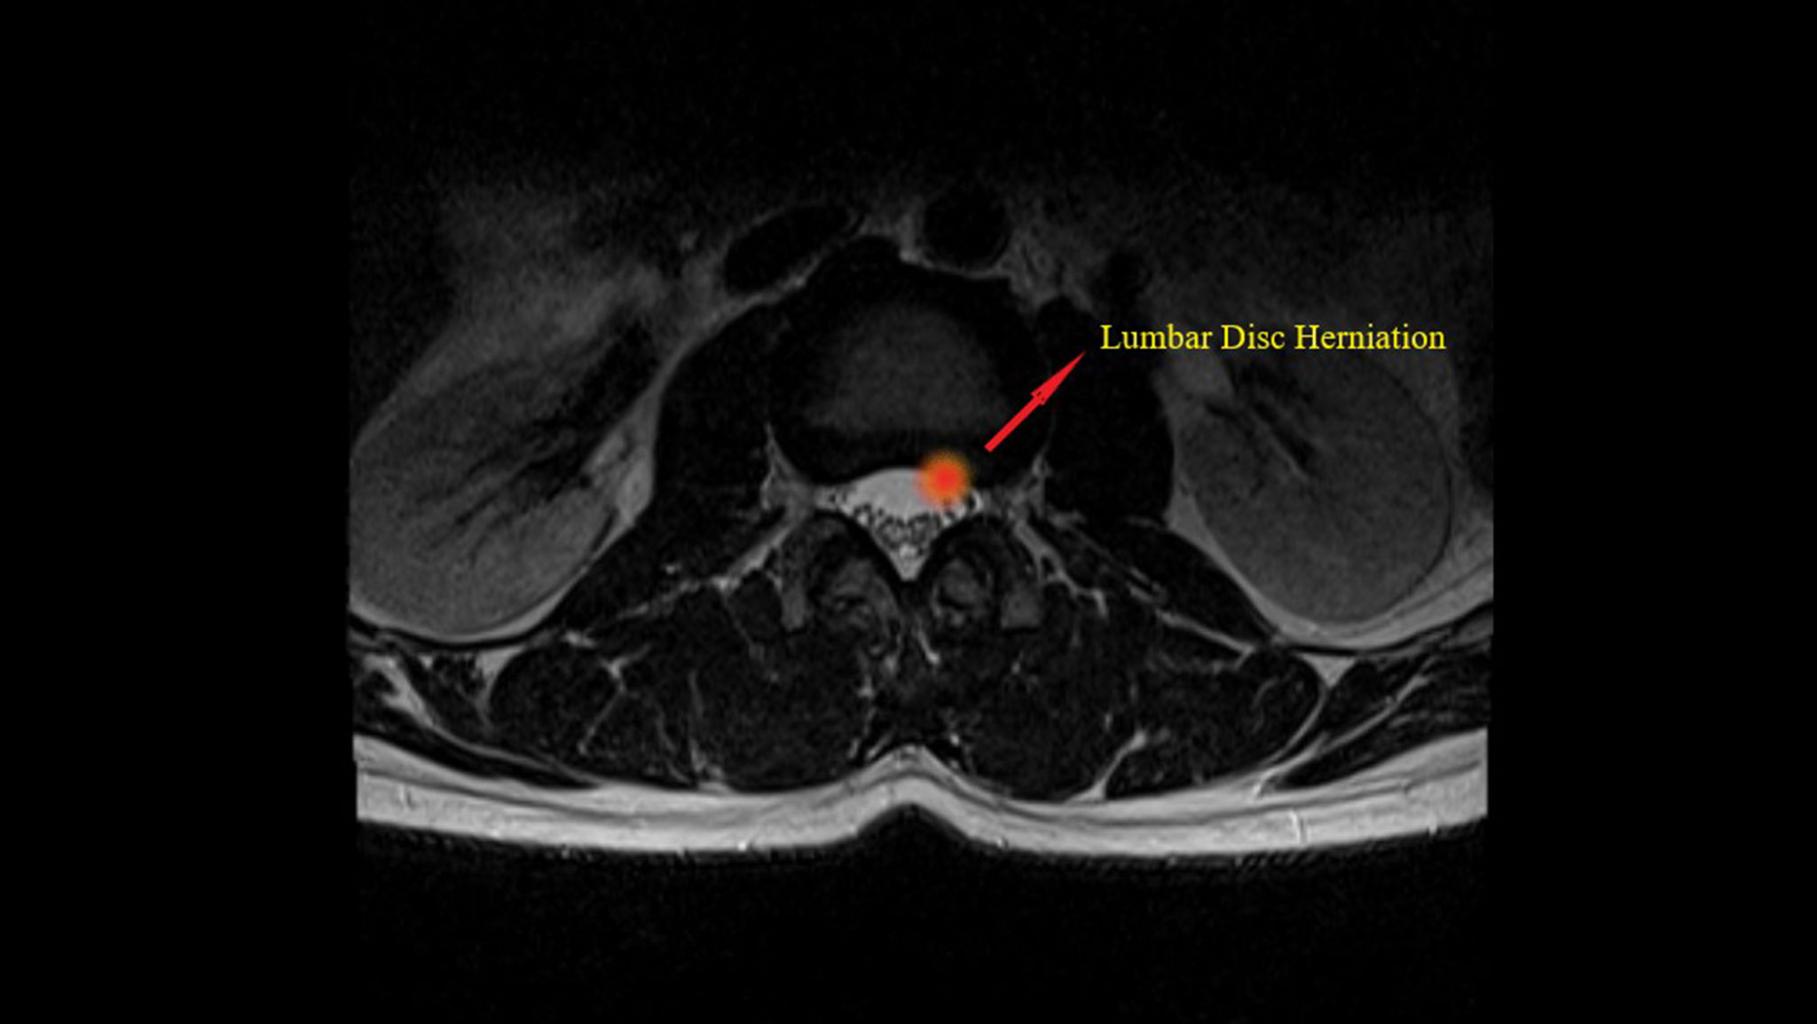

- Herniated disc

- Bulging disc